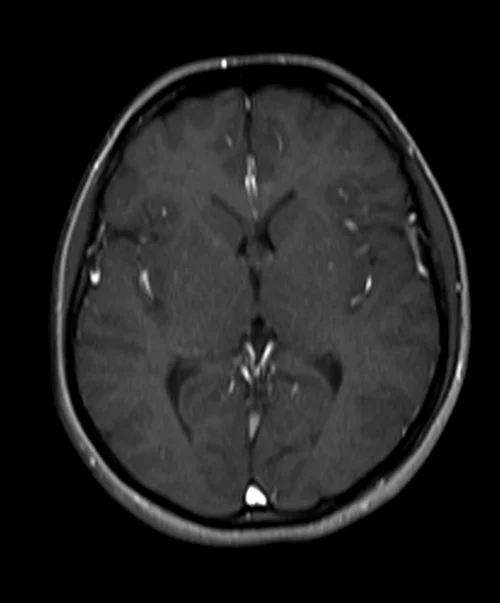

brain mri localizer image